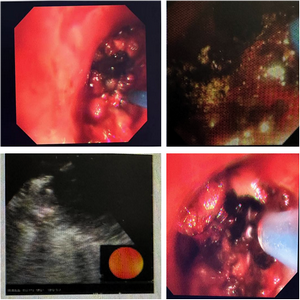

在呼吸与麻醉团队的共同努力下,高难手术在麻醉团队的支持配合下如期进行,硬质支气管镜30秒快速进入患者气道内,镜下见左、右主支气管均被巨大肿瘤横亘,这颗肿瘤几乎将大爷左、右主支气管完全堵死,只留一条微小的缝隙。

右主支气管

患者气道病变复杂,术中软硬支气管镜结合联合氩气刀+激光消瘤术,为患者打通呼吸生命线,于右中间段支气管应用超声支气管镜引导激光消融增大淋巴结,手术过程复杂,难度系数大,需要术者掌握多种镜下治疗手段,手术由顾少岩主任与兰冰医生共同完成,麻醉科孙宝文主任团队一路护航,历时2小时余,顺利结束,术后患者呼吸状态较前明显改善。